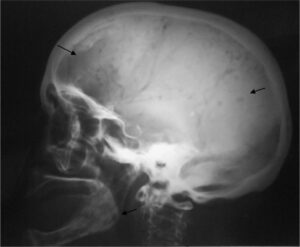

El mieloma múltiple es una enfermedad en la que las células plasmáticas, que normalmente forman parte del sistema inmunológico, comienzan a multiplicarse sin control.

Estas células anormales forman tumores dentro de los huesos, debilitándolos considerablemente:

“La enfermedad genera lesiones óseas, anemia, problemas renales y un sistema inmune comprometido. Su detección suele ser tardía, lo que retrasa el inicio del tratamiento y reduce las posibilidades de controlar su avance”.